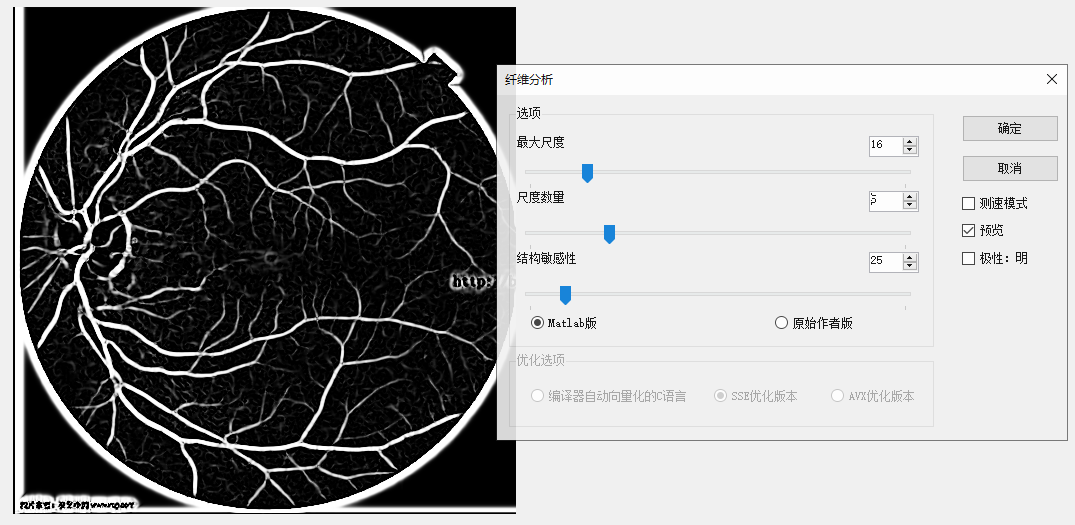

那一副醫學圖像做測試,效果確實不錯:

原圖 尺度數量為5,最大尺度為16的結果

同樣參數原始作者版本的結果,明顯沒有maltab的清晰